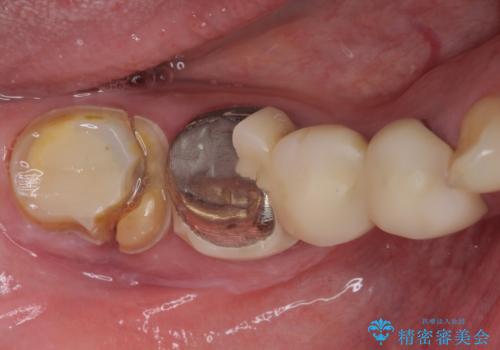

- 近医で奥歯が割れているので抜歯が必要と言われたとのことで来院された患者様です。

診断の結果、歯根が縦に破折しており抜歯が必要な状態でした。

抜歯してからインプラント埋入までには時間がかかるため、その間に下顎左右臼歯の金属のブリッジをオールセラミックへ変えていくこととしました。